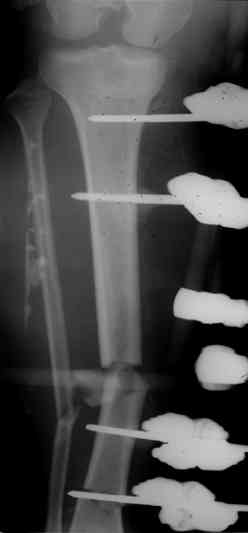

И тракцию бедра на стержне. Типа (СМ картинки).

После выращивания регенерата стержень блокировать.

После заживления раны на левом бедре. Выполнить открытую реподицию и синтез пластиной для дистального бедра. Пластину в проксимальном направлении зафиксировать монокортикально.

А затем выпонить остеотомию бедра в верхней трети.